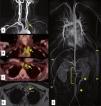

ClasificaciónEn esta actualización se introducen los principales elementos que forman parte de su definición y su categorización en vasculitis de vaso grande, vasculitis de vaso mediano y vasculitis de vaso pequeño. Esta estratificación es útil para ayudar al clínico en el diagnóstico diferencial, en base al territorio vascular donde se sospecha la vasculitis y las técnicas (imagen trasversal, imagen metabólica, arteriografía, biopsia) necesarias para evidenciarla.

Vasculitis de gran vasoSe describen con detalle los principales aspectos epidemiológicos, clínicos, diagnósticos, terapéuticos y pronósticos de las vasculitis de gran vaso: arteritis de células gigantes y arteritis de Takayasu.

Large vessel vasculitisThe main epidemiologic, clinical, diagnostic, therapeutic and prognostic aspects of large vessel vasculitis, including giant-cell arteritis and Takayasu arteritis, are described in detail.